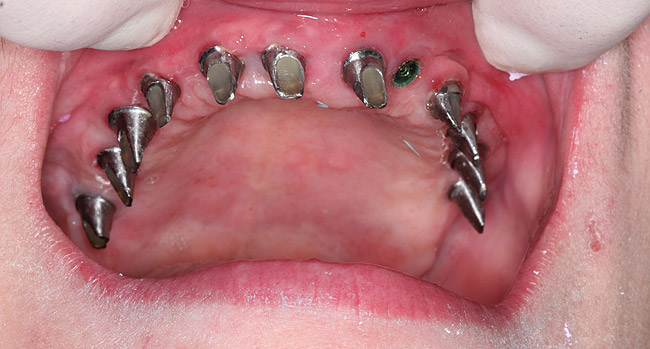

After 6 months of healing, a CBCT scan was taken and good bone formation was seen on the axial (Figure 18) and panograph (Figure 19) views. The CBCT was then used to plan for placement of dental implants (Figure 20). Upon full-thickness reflection of the ridge, abundant bone contour was observed. Internal hex dental implants (BioHorizons) were placed according to the locations planned on the CBCT (Figure 21). After a healing period of 4 months, the implants were uncovered (Figure 22) and abutments were placed (Figure 23). A panograph taken 1 year after this stage revealed the final restorations on well-integrated implants (Figure 24). The patient’s smile reveals a fixed prosthesis that simulates her natural teeth (Figure 25).

Figure 22  Clinical view of implant uncovering with healing caps.

Figure 22